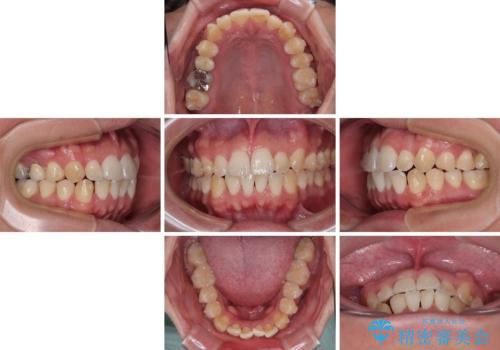

前歯のデコボコをささっと治す 短期間でのインビザライン矯正治療

- 前歯の反対咬合などを気にして来院された患者様です。

ワイヤー矯正、マウスピース矯正どちらでも対応可能であったので、ご本人の希望によりインビザラインにて矯正治療を行うこととしました。

毎日の装着時間をしっかりと守ってくださり、1年強の短期間で、あっという間に治療を終えることができました。